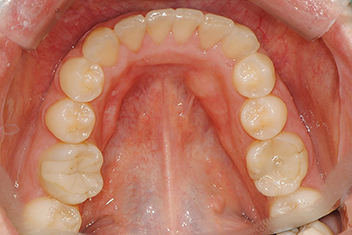

치열 개선 케이스

치료 기간18개월

전반적인 치열 불규칙을 투명교정으로 완전 개선